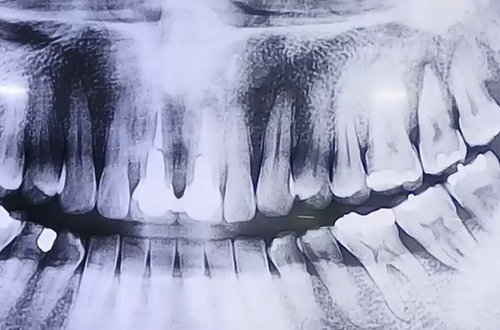

BEFORE

오른쪽 어금니의 불편함으로 내원해주셨던 환자분입니다.

검사를 해 보니 왼쪽 치아 상태가 눈으로도 흔들림이 보일만큼

많이 좋지 않았고, 그 탓에 오랫동안 오른쪽으로만 지속적으로

음식을 씹어 드시다 보니 오른쪽 치아도 안 좋아진 것이었는데요.

근본적인 원인이 왼쪽 위 어금니의 잇몸에 있었던 것입니다.